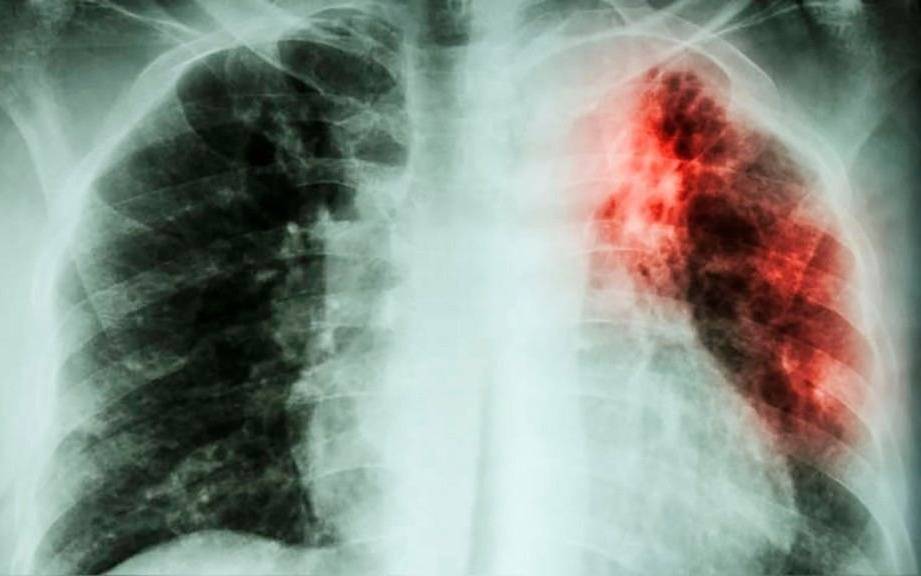

El brusco y preocupante aumento de casos de turberculosis en la Argentina, que se incrementó en un 38 por ciento respecto al promedio registrado en los diez años anteriores, en situaciones que las fuentes médicas relacionan a la caída en las tasas de vacunación y al debilitamiento integral de los sistemas de salud, debiera obligar a las autoridades sanitarias a promover medidas eficaces para revertir este alarmante repunte.

Como expuso el Boletín Epidemiológico Nacional, a mediados de abril pasado se habían notificado ya 3.488 nuevos casos de tuberculosis en el país, una cifra que supera ampliamente la mediana de los cinco años previos, que era de 2.530. Este incremento no es un hecho aislado: refleja una tendencia creciente que se viene consolidando desde hace más de una década, y que se aceleró tras la pandemia de COVID-19.

La tuberculosis es una enfermedad infecciosa causada por el bacilo de Koch que se transmite a través del aire al toser, estornudar o hablar. Afecta principalmente a los pulmones, pero puede comprometer otros órganos. Y aunque es prevenible y curable, sigue siendo un problema de salud pública, especialmente en contextos de hacinamiento, pobreza o acceso desigual a la salud.

El crecimiento sostenido de la tuberculosis constituye una señal de alarma que requiere respuestas urgentes y coordinadas. Lo real es que la tuberculosis vuelve a presentar un panorama de real emergencia sanitaria, a la que no se le estaría prestando una debida contención.